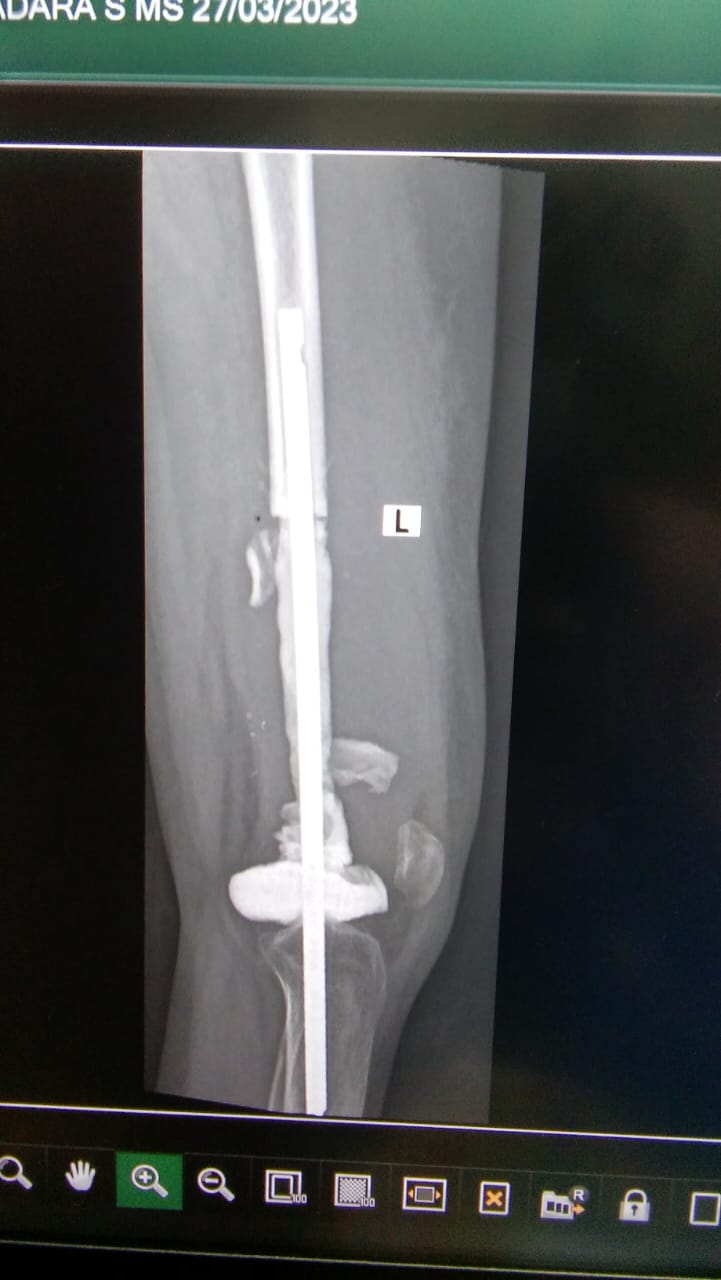

G V S Madara, 19 years old girl, was diagnosed with osteosarcoma (born cancer) of the left distal femur. The surgery of megaprosthesis fixation (artificial joint replacement) was done after the completion of her chemotherapies. The trust contributed towards expenses for his treatment.